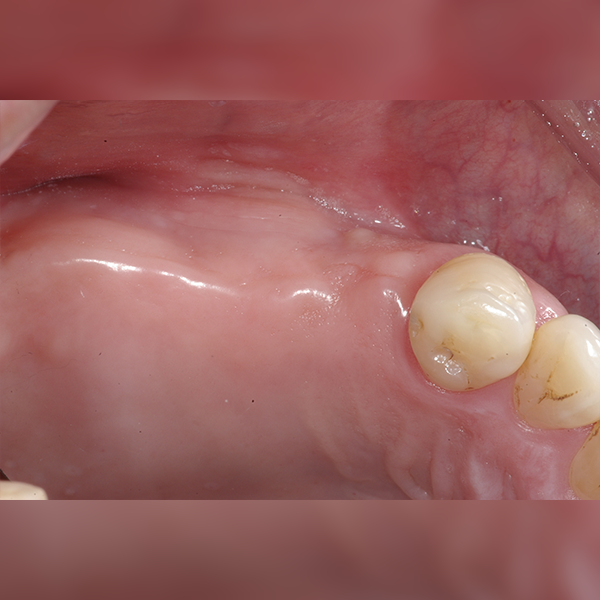

상악/어금니 부분 / 4개이상 / 뼈이식|수면|고혈압

症例.260 [動画] 30代 パク*ソン 2010-10-07 / 2011-04-19

Before Before

After After